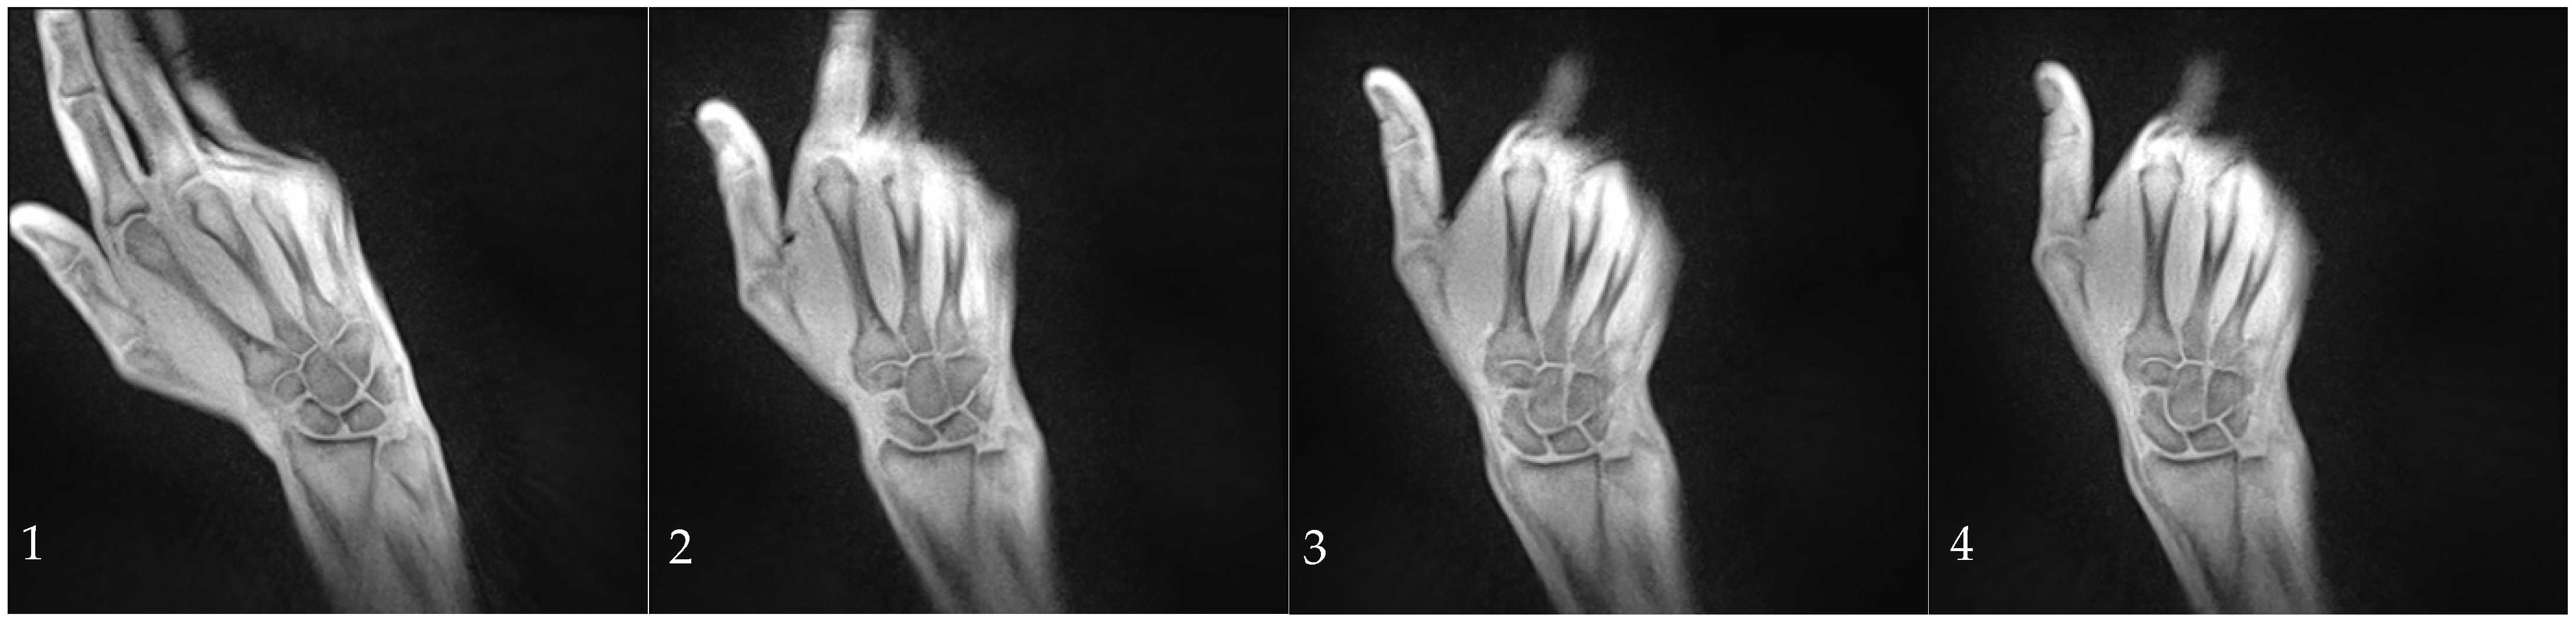

In the dynamic sequences, the SL width was determined every ten images. The extend and direction of movement in the radial or ulnar direction were determined by the angle formed between a line from the styloid process of the radius to the ulnar edge of the radius and the extension of the third metacarpal bone. The angle increased during ulnar movements and decreased during radial movements (Figure 3). The wrist angle remained constant during the fist clench maneuver and was therefore determined only once.

Figure 3. Measurement of the wrist angle determined by the extension of the third metacarpal and the distal radial joint line.